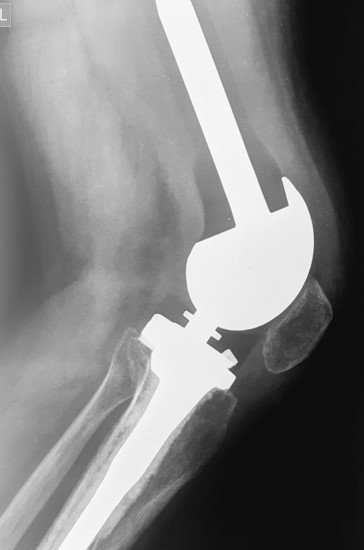

5. Хондросаркома бедренной кости

37-летний пациент обратился в клинику с жалобами на боли в области верхней трети бедра. В ходе обследования была диагностирована хондросаркома бедренной кости. Учитывая, что данный вид опухоли не поддается химиотерапии, специалисты рассмотрели два варианта операции: ампутацию, операцию с сохранением органа. С учетом нечувствительности данного варианта опухоли к лекарственному и лучевому лечению выбор стоял между проведением ампутации (которую рекомендовали в ряде зарубежных клиник в ходе телеконсультаций ввиду выраженного мягкотканного компонента) и органосохраняющим вмешательством. Произведено хирургическое лечение – сегментарная резекция бедренной кости и коленного сустава, замещение дефекта индивидуальным эндопротезом. Спустя 7 лет после операции пациент жив, местного рецидива и отдаленных метастазов заболевания не выявлено, функция оперированной конечности оценивается на «отлично».

До операции

После операции